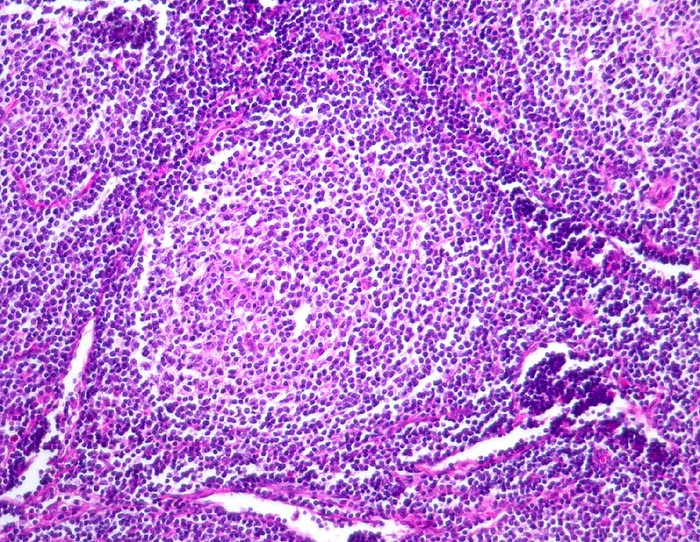

PathoPic – image database / PathoPic ID 3880 - Follikuläres B-Zell Non-Hodgkin-Lymphom

Follikuläres B-Zell Non-Hodgkin-Lymphom

Neoplastischer Follikel mit unscharfer Begrenzung. Eine dunklere Mantelzone ist nicht erkennbar. Das Follikelzentrum ist auffallend monoton. Es fehlen die Kerntrümmermakrophagen, welche für reaktive Keimzentren typisch sind.

Die Keimzentren sind immunhistochemisch positiv für bcl-2.